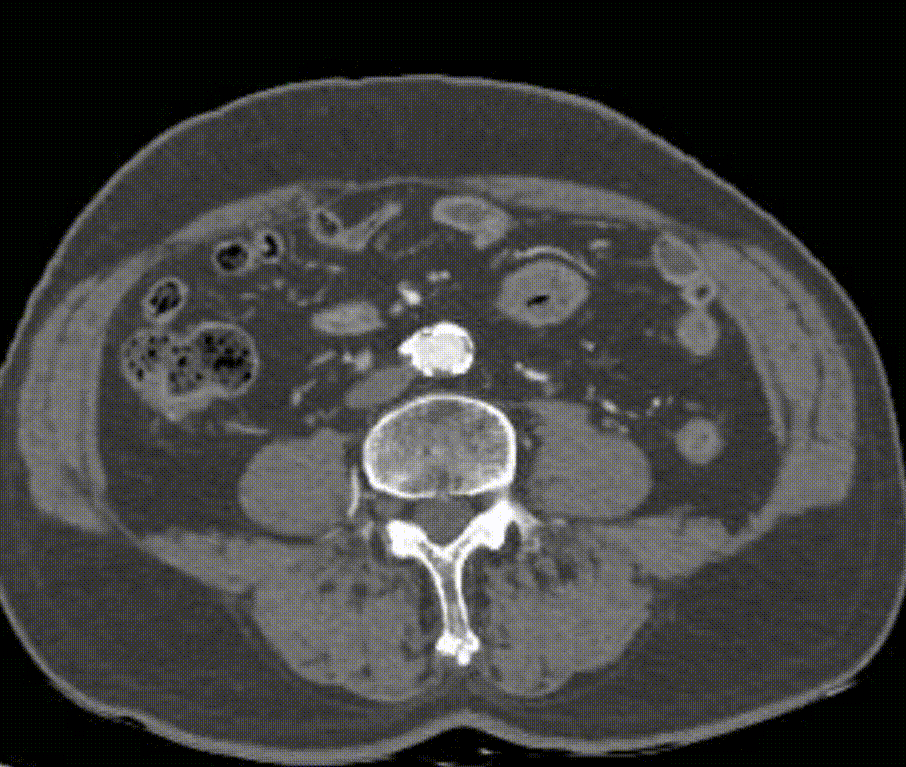

经导丝送入IVUS导管,股浅动脉近段重度狭窄、钙化明显,狭窄率大于90%

股浅动脉中远段及腘动脉重度狭窄、环周钙化明显